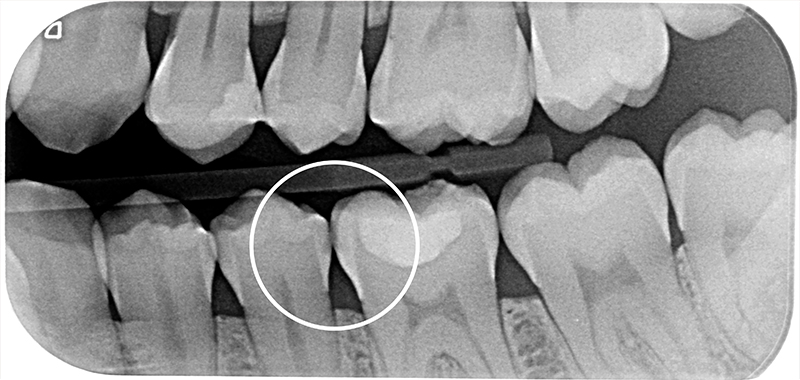

In fase di trattamento restaurativo del 36 mesiale, la paziente viene trattata con una singola applicazione di CURODONT™ REPAIR sul 35 distale. Una volta concluso il trattamento, alla paziente vengono fornite le istruzioni di igiene orale di routine e le viene consegnato un tubetto di CURODONT™ PROTECT (Fig. 9). Sei mesi dopo il trattamento, alla visita di follow-up, si osserva radiologicamente la regressione della lesione.

Fig. 8 - Immagine della lesione prima dell’applicazione di CURODONT™ REPAIR.

Fig. 9 - Immagine radiografica a distanza di 6 mesi dall’applicazione di CURODONT™ REPAIR.